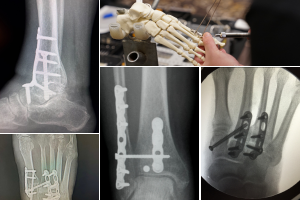

The Advanced Principles of Foot and Ankle Trauma course covers the principles and current concepts in the treatment of more complex injuries and complications for doctors of podiatric medicine (DPMs), incorporating the latest techniques in operative fracture management.

Before attending the course, participants complete a self-assessment questionnaire and view a series of online, prerecorded presentations related to the 4 areas addressed during the course (available September 2024). The face-to-face course contains evidence-based lectures and small group discussions to further develop decision-making and management skills. During the practical exercises, participants will be trained in the application of fixation techniques for several specific fractures in the foot and ankle.